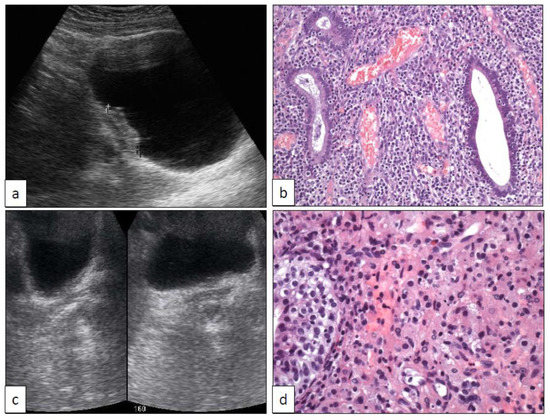

14. Florid von Brunn Nest Proliferation (VB), Cystitis Cystica (CC), and Cystitis Glandularis (CG)